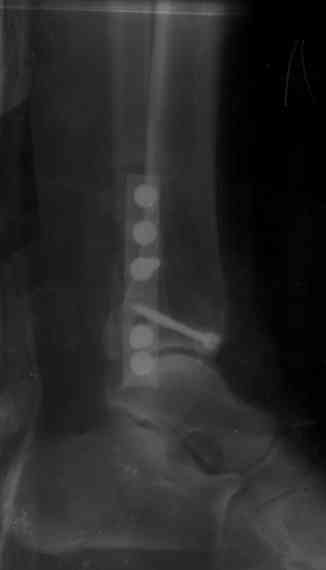

На 4-й неделе убрал спицы, с 7-й недели начал ЛФК, дозированную нагрузку, физиопроцедуры, массаж. Назначил хондропротекторы. Получилось вот что.

Удалены спицы, а гипса не было? 3-х лодыжечный перелом фиксировать 4 недели недостаточно. Что и подтверждается на последнем снимке - есть тенденция к подвывиху кнаружи, кзади... Что будет дальше, когда пациент начнет давать полную нагрузку?

Иммобилизировал ортезом, коллеги из области подарили.

Я вижу, вы сторонник раннего оперативного лечения и стабильной фиксации при таких переломах. Согласен, однако нельзя забывать о возрасте

пациента, трудовой деятельности и желания. В данном случае (60 лет пациентке), я склоняюсь к мнению, что данная методика наиболее

приемлема. У более молодых предпочтительным считаем стабильную фиксацию (операция

выполняется в первые 3-5 часов после травмы, что позволяет избежать травматического отека и соответствующей отсрочки лечения на 2-2,5

недель)

Понаблюдаю за пациенткой 1-2 года, посмотрим.

|

СМ> На 4-й неделе убрал спицы, с 7-й недели начал ЛФК, дозированную

СМ> нагрузку, физиопроцедуры, массаж. Назначил хондропротекторы.

СМ> Получилось вот что.

Малоберцовая выглядит коротковатой. Профиль как-то мутный. Вообще, неплохо было бы сделать снимки в сравнении со здоровой.